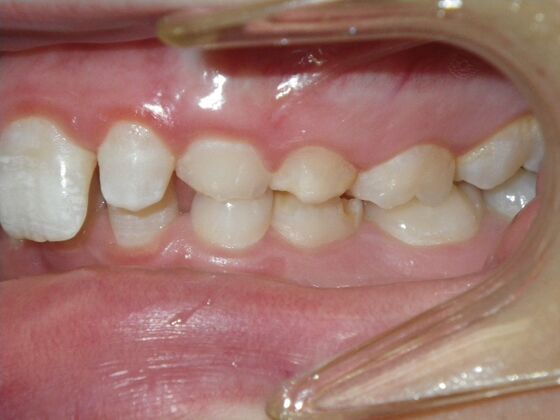

This patient does not like his anterior deep bite and the flaring of the right lateral incisor as well as anterior spacing. The solution was to correct his Class II molar relationship, Division II and deep anterior bite and close spacing as much as possible with addition of composite restorations on distals of lateral incisors. We began with utility archwires, eventually correcting Class II molar with distalizing appliance, and continued with final tip and torque. All that is left now is to ad composite to distals of upper lateral incisors.